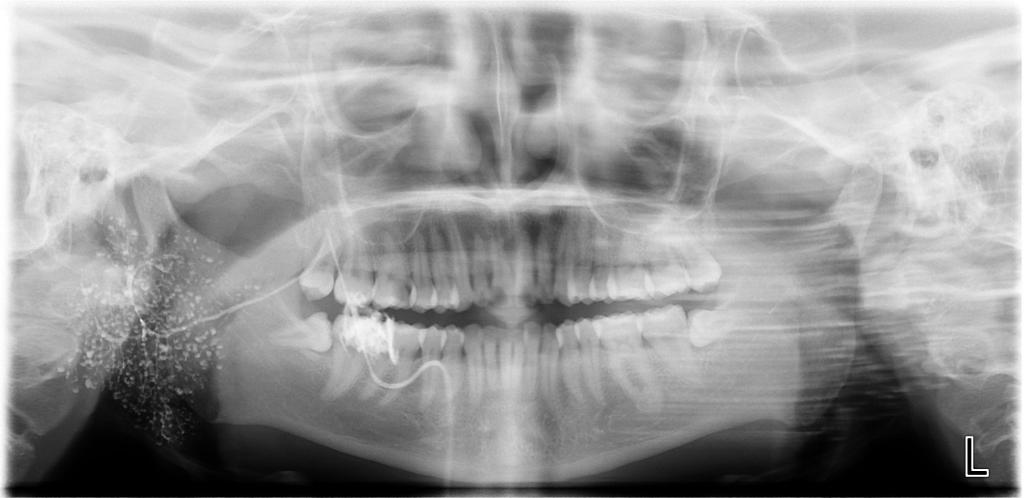

数字化口腔曲面体层片

诊断范围涉及牙体牙髓病、牙周病、阻生牙/多生牙定位、种植牙术前CT评估分析、颞下颌关节CT诊断分析、,颌骨及涎腺疾病、颌面发育畸形、正畸治疗辅助诊断等大部分颌面部疾病,为临床医疗提供强有力的支持。